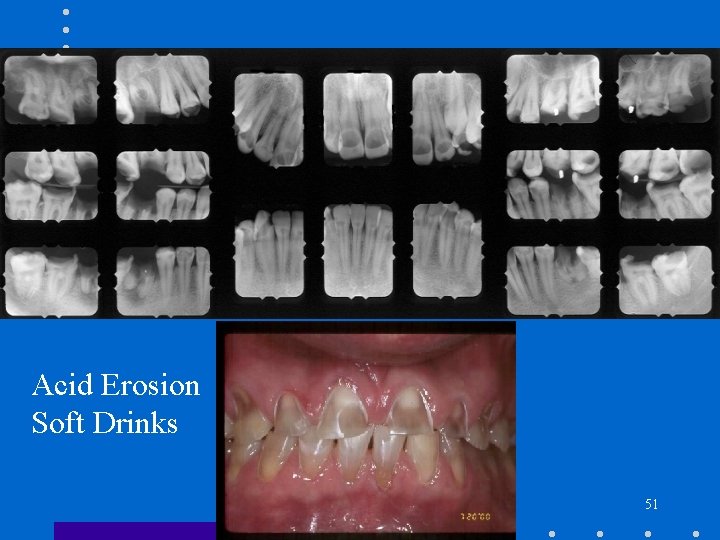

Erosion • • • Chemical cause No bacteria involved Diet Regurgitation Occupational hazards 49

Erosion - Radiologic Features • • Radiolucent defects Dietary acids – labial surface Regurgitation – mandibular lingual surface Occupational – all surfaces 50

Acid Erosion Soft Drinks 51